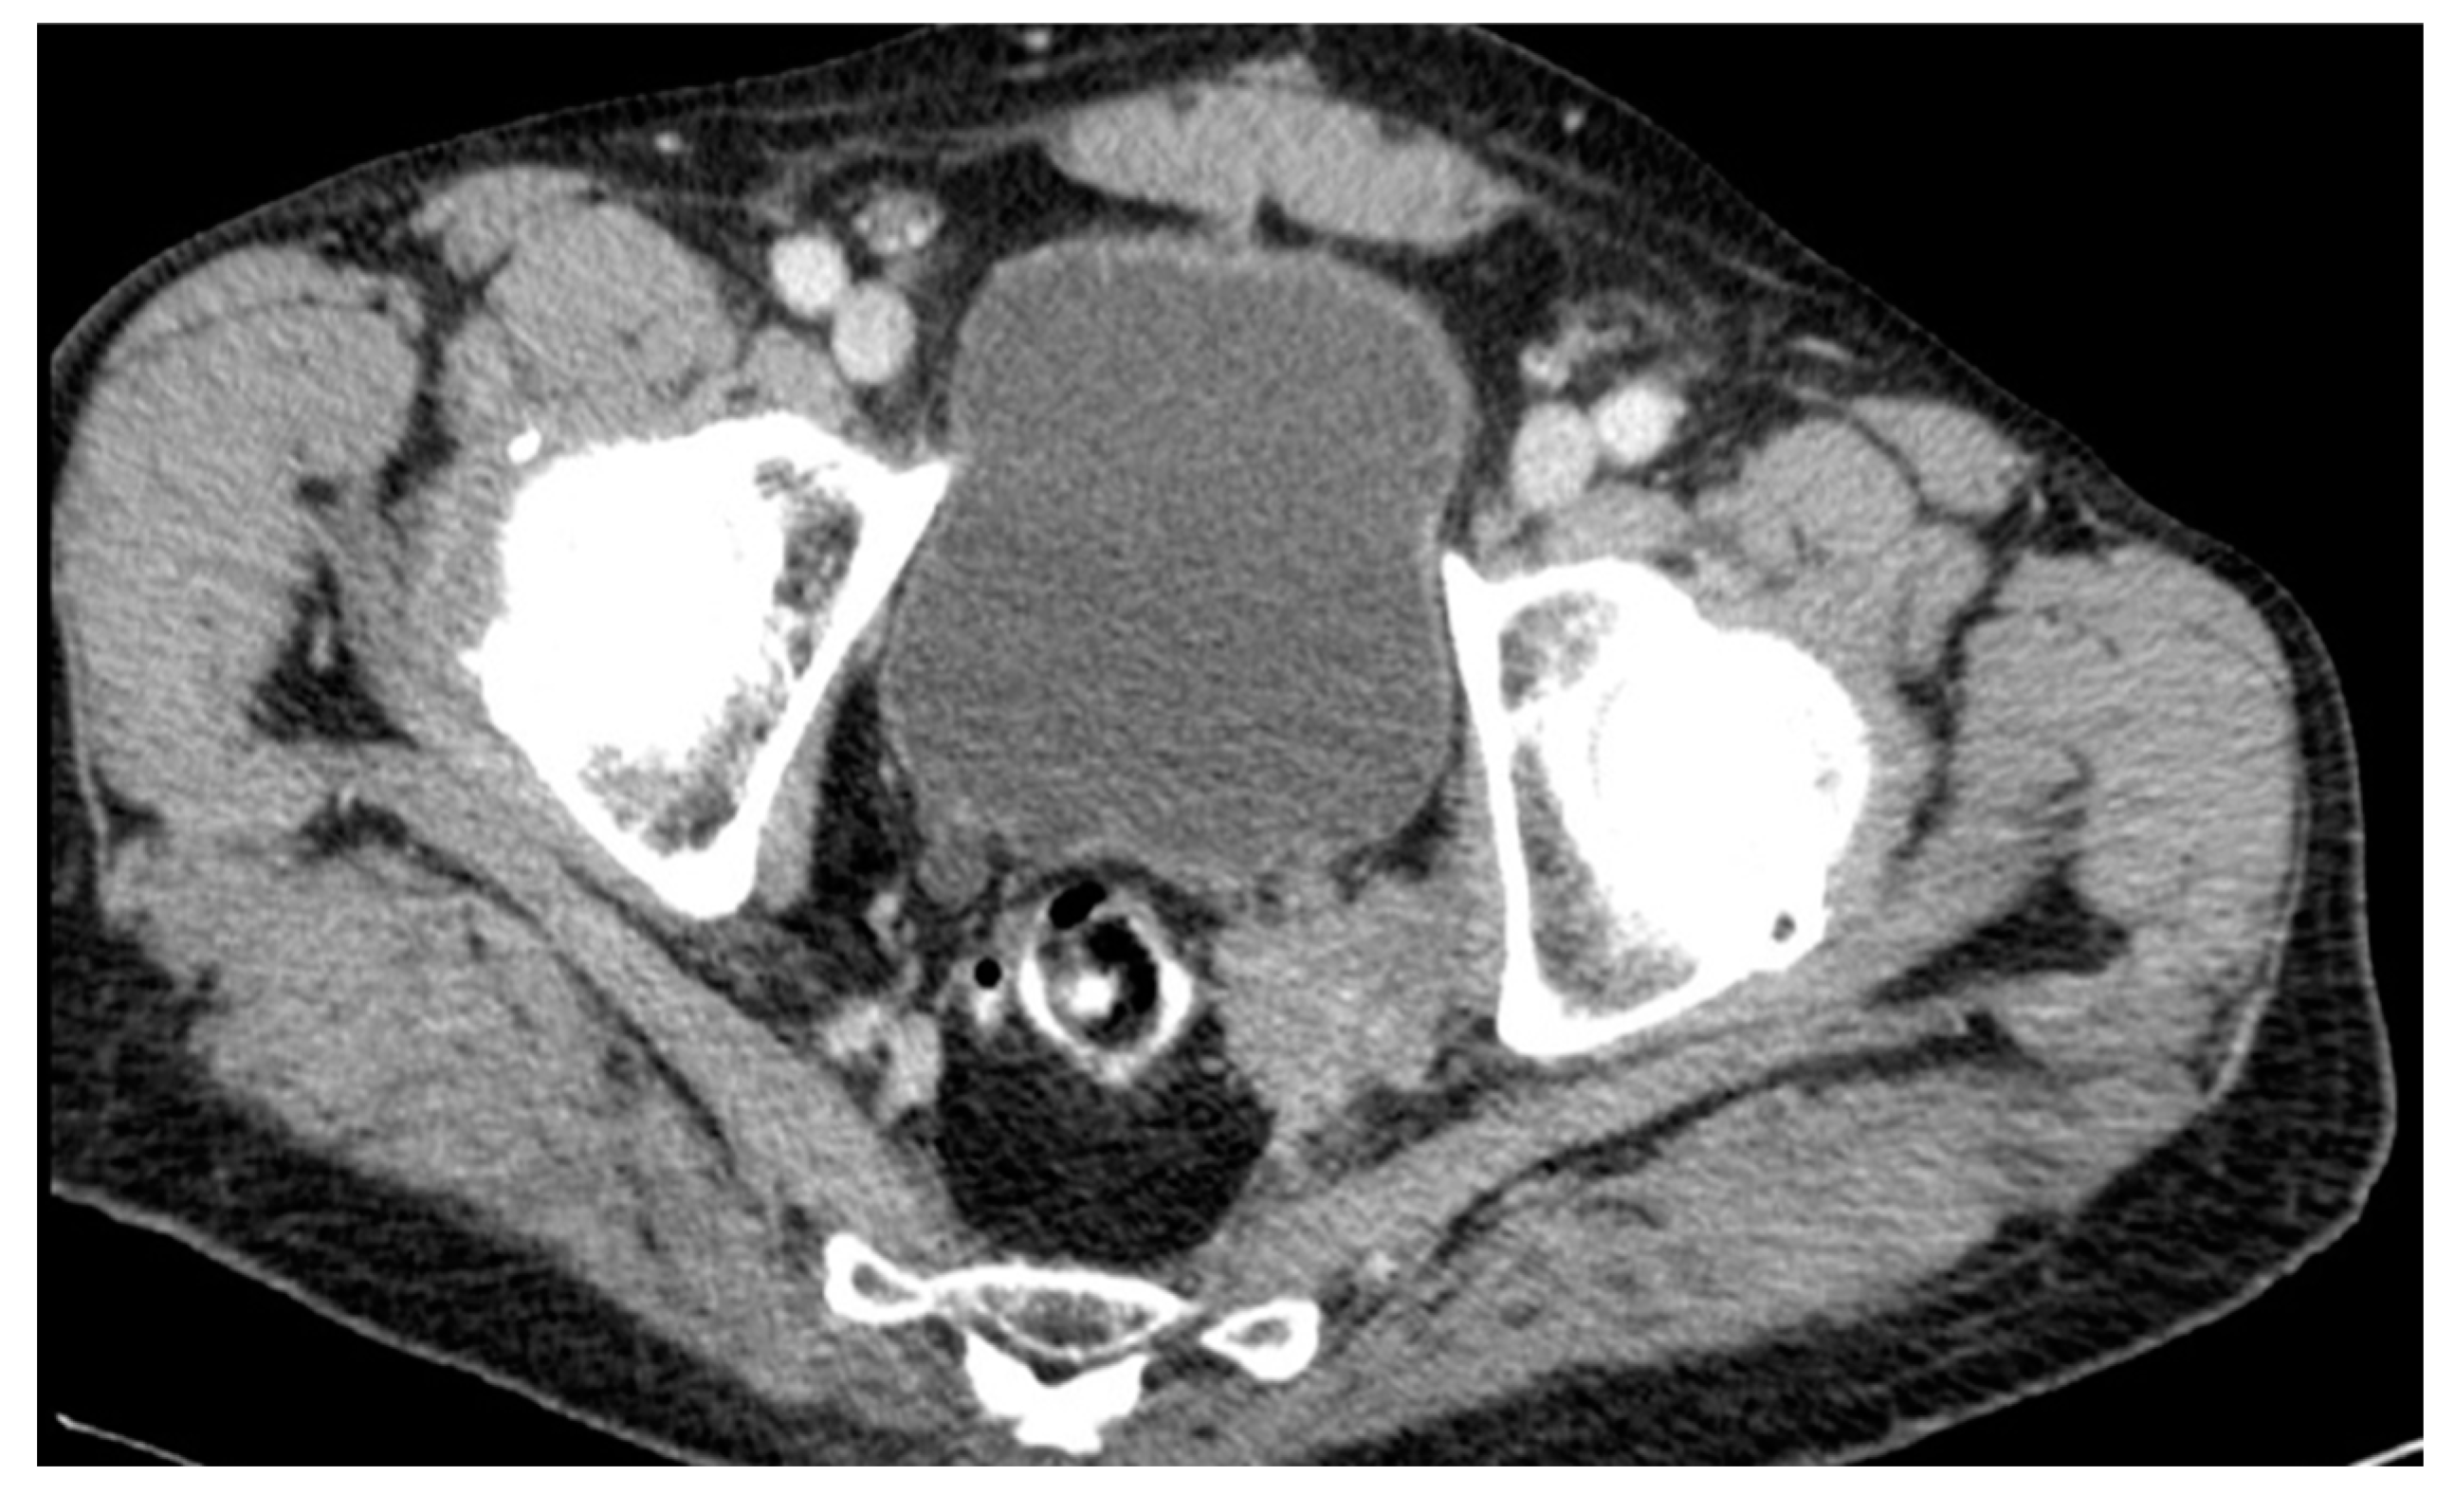

A lateral local recurrence with infiltration of the ureter and bladder was found in a male patient after AR in July 2001. The initial histological finding revealed an ypT2ypN1-tumor. Adjuvant therapy was recommended but was refused by the patient. The five years of regular follow-up were unobtrusive. Eventually, the patient underwent further diagnostic investigation in 2012 because of elevated tumor markers (CEA levels). A CT scan confirmed recurrence in the pelvic wall 135 months after surgery (see Figure 7). The tumor was histologically confirmed through transanal biopsy. The therapy consisted of an extended surgery with resection of the urethra and bladder after local radiation and chemotherapy, but an R0-resection could not be achieved. Furthermore, the patient developed lung metastases and received radiotherapy. The patient died 5 years after diagnosis of local recurrence in 2017.

Figure 7. CT scan #1.